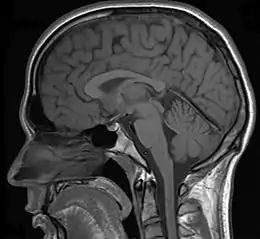

MRI image

Various studies have used MRIs (magnetic resonance imaging) to measure brain activity when individuals detect (or fail to detect) a change in the environment. When individuals detect a change, the neural networks of the parietal and right dorsolateral prefrontal lobe regions are strongly activated.[32][33] If individuals were instructed to detect changes in faces, the fusiform face area was also significantly activated. In addition, other structures such as the pulvinar, cerebellum, and inferior temporal gyrus also showed an increase in activation when individuals reported a change.[33] It has been proposed that the parietal and frontal cortex along with the cerebellum and pulvinar might be used to direct an organism's attention to a change in the environment. A decrease of activation in these brain areas was observed if a change was not detected by the organism.[32] Furthermore, the neurological activation of these highlighted brain areas was correlated with an individual's conscious awareness of change and not the physical change itself.[33]

Other studies using fMRI (functional magnetic resonance imaging) scanners have shown that when change is not consciously detected, there was a significant decrease in the dorsolateral prefrontal and parietal lobe regions.[32] These results further the importance of the dorsolateral prefrontal and parietal cortex in the detection of visual change. In addition to fMRI studies, recent research has used transcranial magnetic stimulation (TMS) in order to inhibit areas of the brain while participants were instructed to try to detect the change between two images.[34] The results show that when the posterior parietal cortex (PPC) is inhibited, individuals are significantly slower at detecting change.[34] The PPC is critical for encoding and maintaining visual images in short term working memory, which demonstrates the importance of the PPC in terms of detecting changes between images.[34] For a change to be detected, the information of the first picture needs to be held in working memory and compared to the second picture. If the PPC is inhibited, the area of the brain responsible for encoding visual images will not function properly. The information will not be encoded and will not be held in working memory and compared to the second picture, thus inducing change blindness.